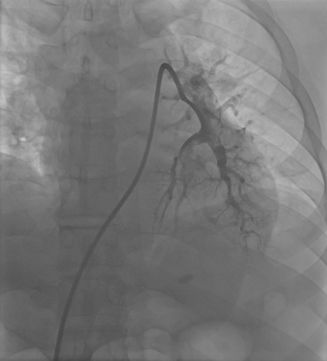

修正诊断:急性肺栓塞。给予阿替普酶50 mg静脉溶栓,之后依诺肝素80 mg ih q12h。复查血气分析:pH 7.5(↑),PCO225.2 mmHg(↓),PO264.9 mmHg(↓),SO294.5%(↓),PO2(A-a)50.0 mmHg(↑)。患者仍觉活动后胸闷,于2014年11月5日行肺动脉造影、肺动脉血栓导管碎解及血栓抽吸,术中测肺动脉压为60/27 mmHg,手推造影剂,可见肺动脉近段多处充盈缺损,先后送入7F长鞘,反复捣碎、抽吸,抽出大量新鲜血栓。再次造影后见肺动脉充盈缺损明显减轻(图2)(图3),测肺动脉压为47/8 mmHg。其后给予阿替普酶50 mg+生理盐水50 ml,2小时静脉泵入。泵入完毕后给予依诺肝素80 mg ih q12h,加用华法林抗凝。术后1周复查肺动脉CTPA示左、右肺动脉主干血栓消失,远端分支少许血栓(图4)。病情好转出院。

图3.捣碎、抽吸后造影肺动脉显影